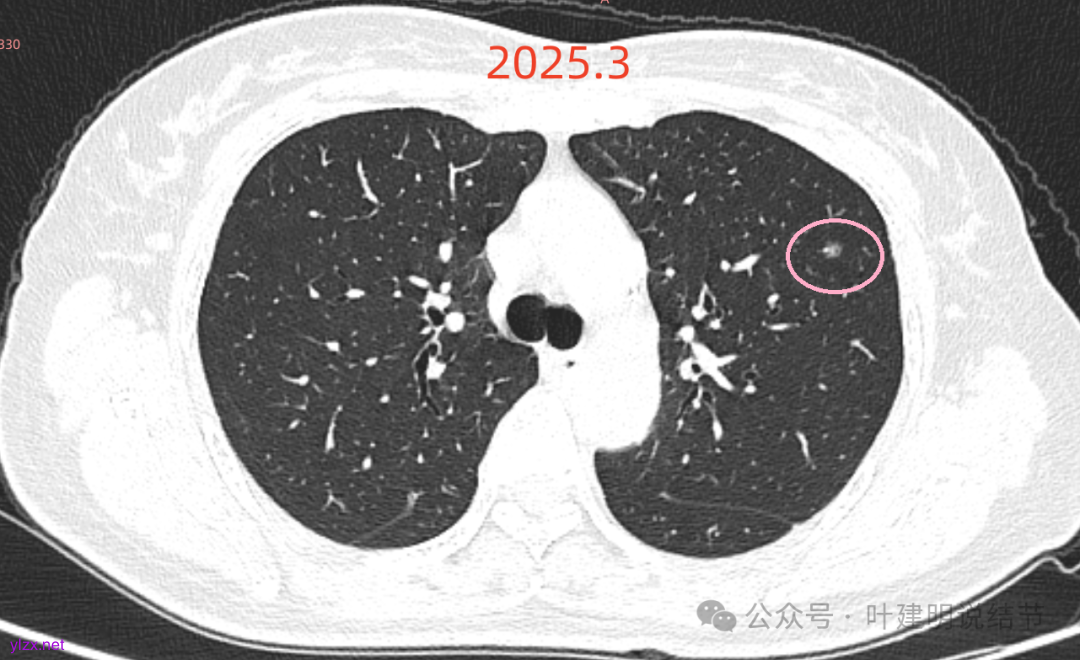

先来看2025年3月的影像:

主病灶矢状位有血管进入,边缘毛糙,密度不纯,倒是更像肿瘤些。

再看2020年5月时的主病灶以及两次对比的影像:

上图示对比,密度略有增加,但并不十分厉害。

两肺多发磨玻璃结节,我们主要看最主要的病灶有没有风险或者有没有进展就可以。我是先看2025年的,黄色的微小磨玻璃结节,密度很低,但是轮廓较为清楚,需要考虑肺泡上皮增生或者肺泡间隔增宽,严格意义上应该没有算肺癌,但是以后有可能会发展到不典型增生或者原位癌,当然也可能永远发展不到那个程度,所以目前不需要管;蓝色的到底是肺泡上皮增生还是少许慢性炎不太好确定,因为轮廓稍显模糊,但它又是磨玻璃密度,总归近期是能够随访的;橘色的密度比黄色的略高,有可能会使肺泡上皮增生或者不典型增生,目前也仍可以随访;粉色的是主病灶,位于左肺上叶,混合密度,表面毛糙,由小血管进入,单次看需要考虑微浸润性腺癌可能性较大。然后我们再来看2020年的影像,因为除了粉色的其他的都没有风险,所以不需要一一去找出来,重点关注粉色这处当时是怎样的。我们发现这个病灶5年前就有,也有小血管进入,也有表面毛糙,也是磨玻璃密度,但是当时磨玻璃当中没有实性的成分,是纯磨玻璃伴微小血管进入。对比起来看,这个病灶在5年当中略有进展,原来应该是腺体前驱病变,现在应该是原位癌或者微浸润性腺癌。那么是不是现在就到了一定得马上手术的程度呢?这个仍然可能是不同医生意见会有出入的。假如说从再随访是不是马上会转移来讲,这么小的肿瘤,发展这么慢,而且仍然含有磨玻璃成分,病理考虑与微浸润性腺癌可能性较大,应该仍然不至于说没有随访的空间。但是如果继续随反思想压力比较大,以及即便在随访后续仍然总得要开刀来说,加上病灶位置靠胸膜并不远,简单的单孔胸腔镜楔形切除就能解决问题,将有一定风险的这个病灶切了,同样是可行的。这需要你自己权衡决定。我没有办法100%给十分确切的意见。但是如果从倾向性来讲,由于是多发病灶,加上年纪还轻,风险还不是很大,稍微清一下雨6~9个月复查,有进展病风险再增加再考虑手术。意见供你参考!